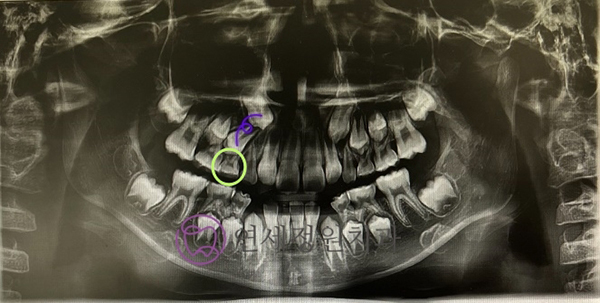

원래도 치아가 늦게 나긴 했지만 하두 유치가 늦게 빠지길래 정기 검진도 할 겸 아들 파노라마 사진을 찍어보았는데, 오른쪽 위 송곳니와 작은 어금니의 관계가 심상치 않아보였습니다! 위 사진에서 보라색 선으로 표시되어 있는 두 치아가 바로 맹출해야 할 송곳니와 첫번째 작은 어금니입니다. 그런데 첫번째 작은 어금니의 맹출 각도가 영 마음에 들지 않았습니다. 반대편과 비교해보면 확실하게 알 수 있는데요. 작은 어금니가 뒤로 기울어져서 나오고 있어서 옆 송곳니가 내려오지 못하고 있었습니다.

아직 유구치의 뿌리도 좀 남아있는 상태라 아직 연두색 동그라미 속 유치가 빠질 시기는 아니었는데, 고민 끝에 유치를 먼저 발치해주기로 했습니다. 유치를 먼저 발치해서 작은 어금니가 빨리 내려올 수 있는 공간을 만들어주기로 했습니다.